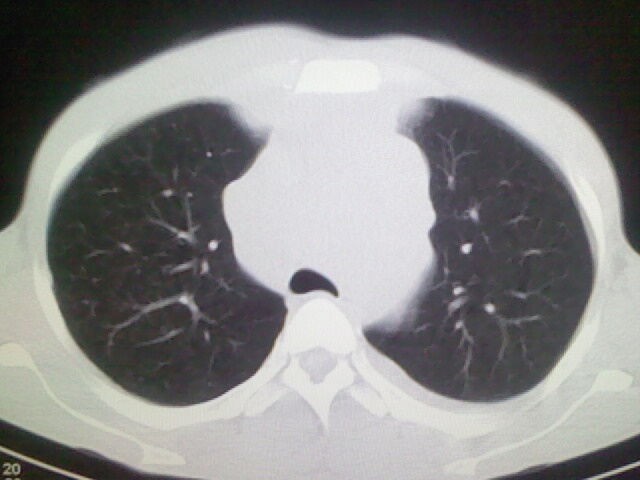

以下是引用杀毒软件在2008-9-3 6:11:00的发言:[br]侵袭性胸腺瘤------一般不侵到气管旁[br][br]考虑----纵隔淋巴瘤,心包及胸膜受累

以下是引用wzr在2008-9-3 5:30:00的发言:[br]侵袭性胸腺瘤

以下是引用随光逐影在2008-9-3 7:07:00的发言:[br]1)考虑淋巴瘤可能。2)双侧胸腔积液(以左侧为甚)。3)心包积液。